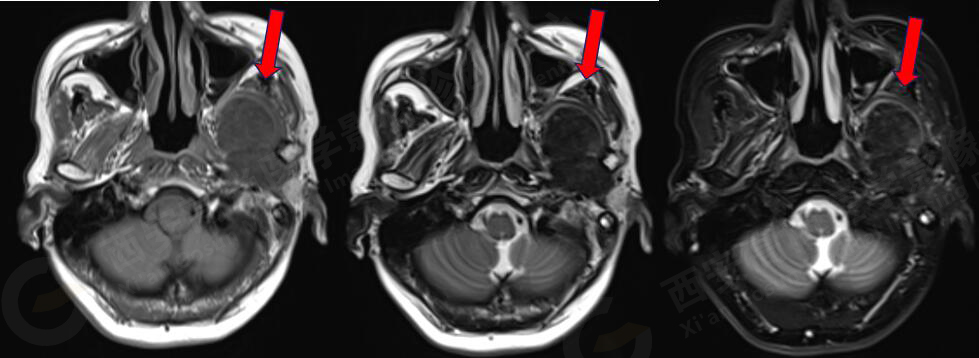

女,58歲,左側(cè)咀嚼肌間隙腫塊,鄰近翼板外側(cè)骨質(zhì)破壞;左側(cè)下頜升支內(nèi)側(cè)占位,皮質(zhì)旁骨軟骨來源。

MR圖像

MR診斷

左側(cè)翼腭窩、顳下窩占位,左側(cè)腮腺受壓變形,頸內(nèi)動脈稍受壓,考慮軟骨組織來源、良性病變。

此腫瘤位于左側(cè)翼腭窩、顳下窩,各序列均呈低信號,與翼突內(nèi)外側(cè)板、下頜骨關(guān)系密切,鄰近下頜骨骨皮質(zhì)破壞,DWI像上呈較高信號,呈不均勻中度強化,因此考慮軟骨來源或肌纖維來源,良性可能性大。